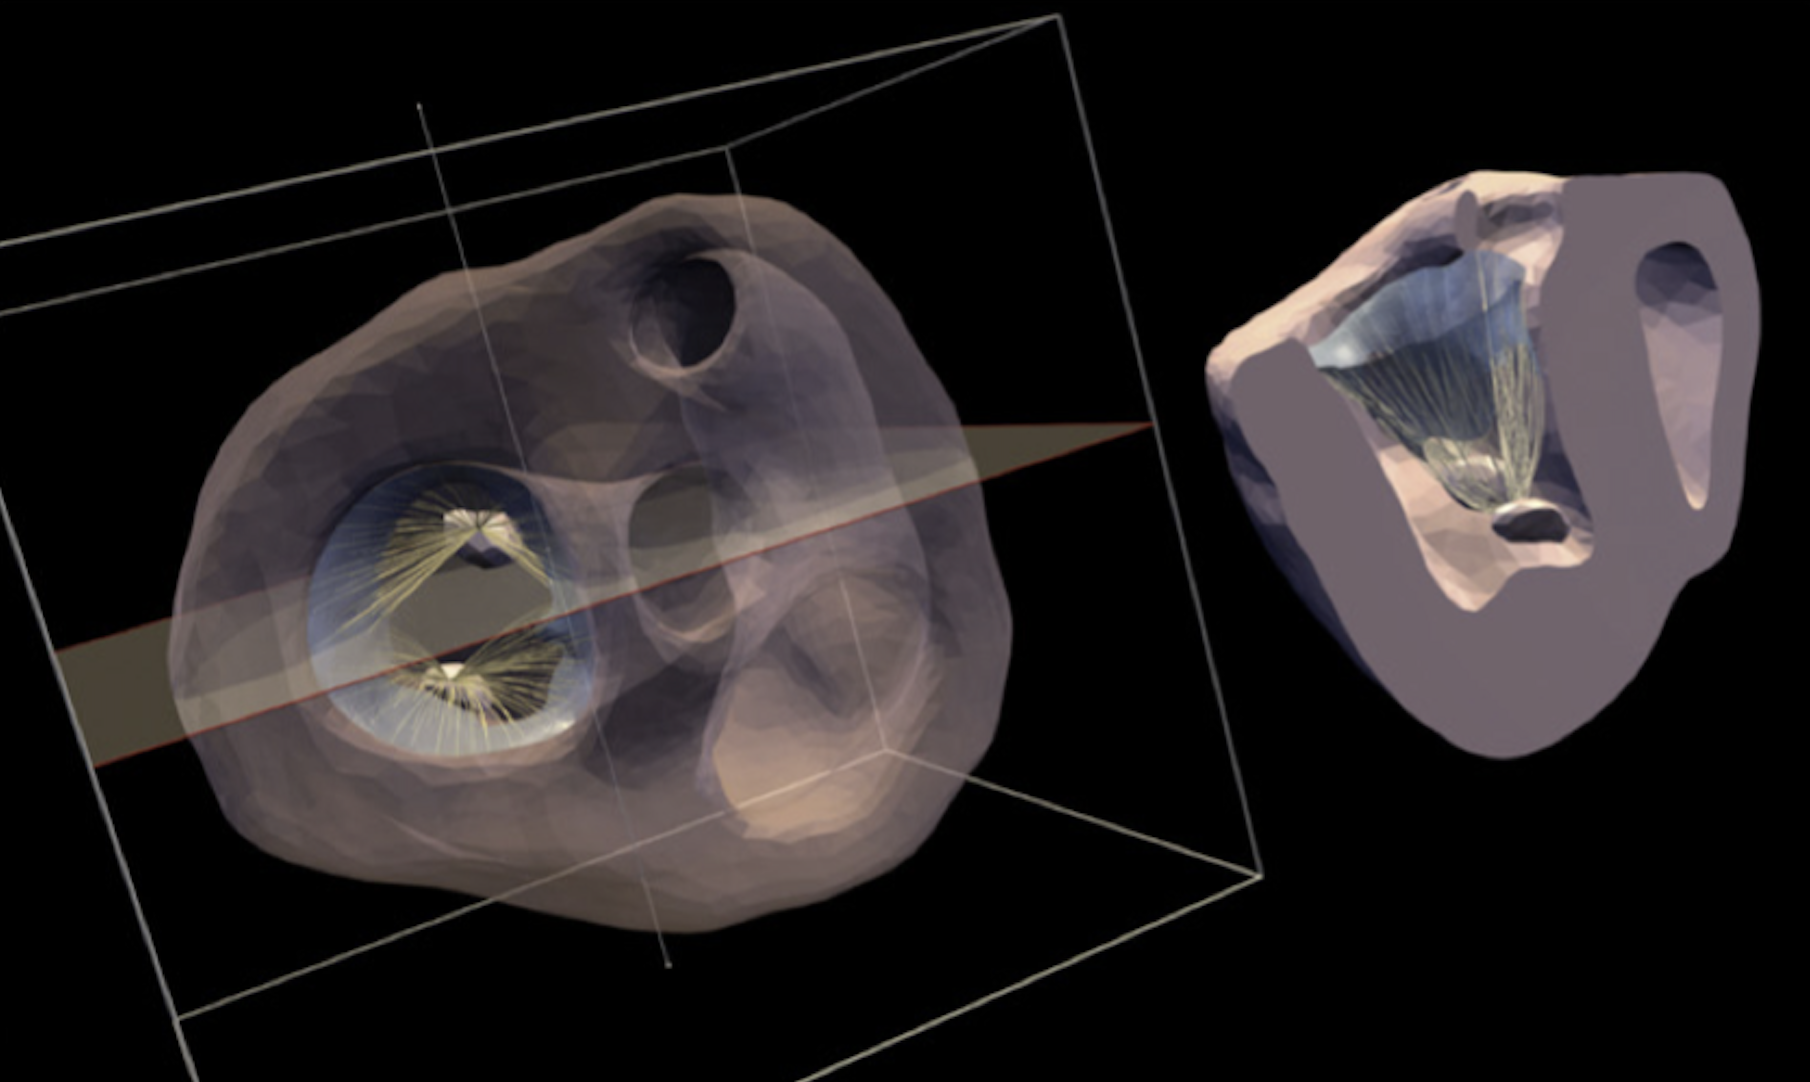

medical imaging